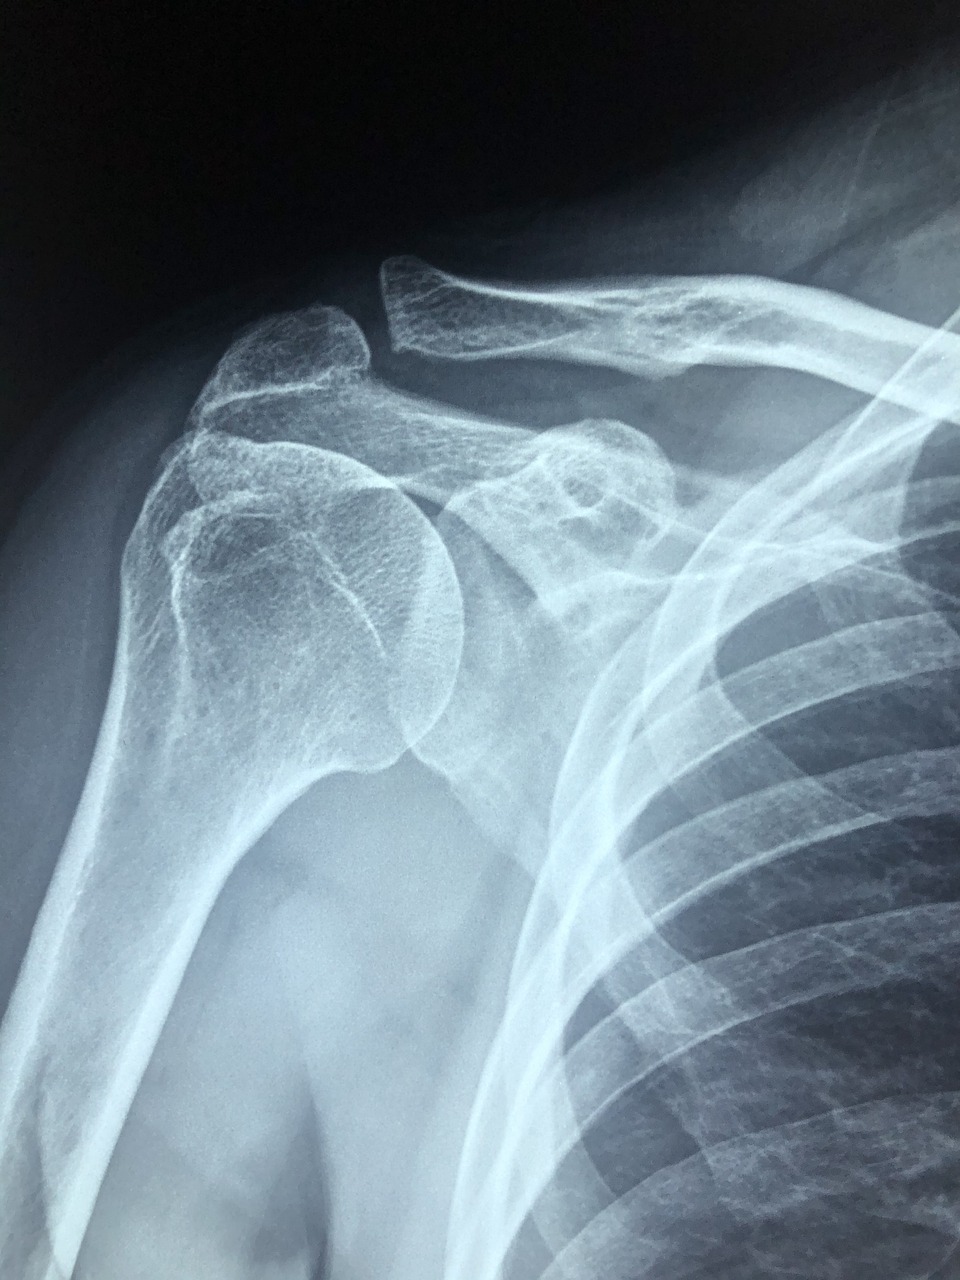

회전근개파열 수술은 파열된 어깨 힘줄을 봉합하는 수술입니다.

이 수술 후 바로 팔을 움직이면 봉합 부위가 다시 찢어질 수 있어요. 그래서 반드시 어깨 보조기를 착용해야 하죠.

보조기는 팔을 고정시켜 수술 부위에 불필요한 자극을 최소화 해줍니다.

특히 수술 직후 4~6주 동안은 손상 부위를 안정화시키는 초기 회복 기간으로, 이 시기 동안 움직임을 최소화하는 것이 필수예요.